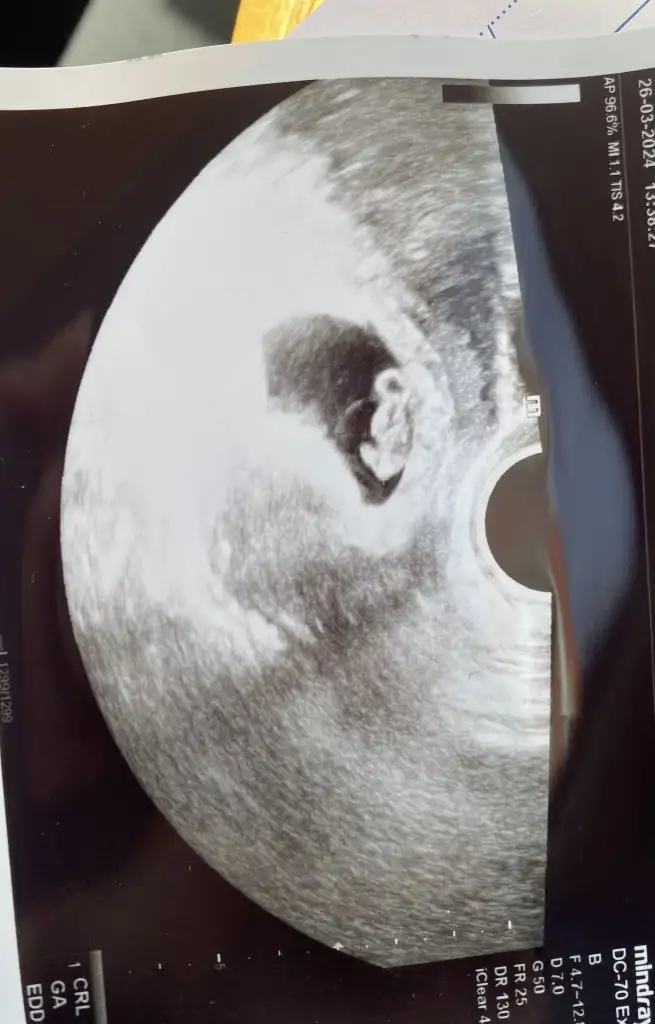

Benim de 2 gundur bulantim azaldi..bilmiyorum nedendir..randevuma daha cok var.cok cok saolun iyi ki varsınız kızlar. o kadar cok şey kafamda kuruyorum ki az da olsa rahatladım.inşallah bebeklerimizi sağlıkla kucagımıza alırız tum bu stresleri unutur gideriz

inşallah normaldir canım. şuan varlığını hissedecegimiz tek şey belirtiler oldugundan onlar da da azalma yok olma olunca direkt kötü düşünüyoruzBenim de 2 gundur bulantim azaldi..bilmiyorum nedendir..randevuma daha cok var.